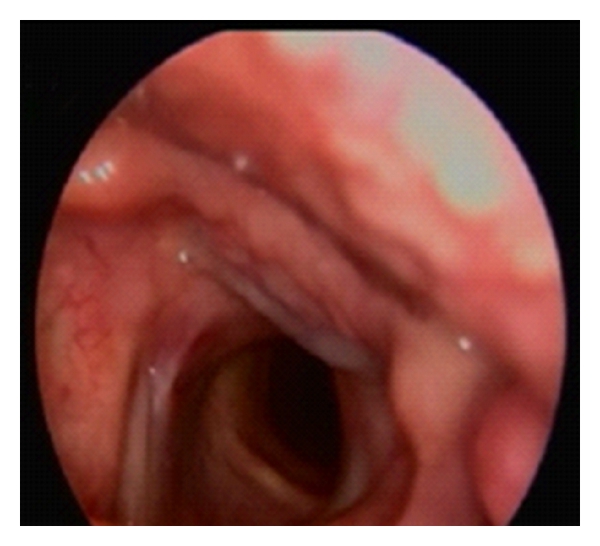

A 60-year-old male patient presented to our clinic with the complaints of hoarseness persisting for one year. He had respiratory distress appearing in the last 3-4 months. His medical history was unremarkable except for history of smoking (1 package per day for 40 years). On his videolaryngoscopic examination, a 1.5 cm vascularized, pedunculated polypoid lesion, originating from the posterior half of the vocal cord and vocal process of the arytenoid, was observed. The mass was obstructing the endolarynx, subtotally (Figure 1(a)). A tracheotomy was performed under general anesthesia to secure the airway. The mass was totally excised by endolaryngeal microsurgery. Postoperative videolaryngoscopic examination on the 4th month revealed a healed incision with no residual or recurrent mass (Figure 1(b)).

(a)

(b)

The most commonly known mesenchymal tumors of the larynx are lipomas, chondromas, vascular tumors, and paragangliomas. Schwannoma originates from the superior laryngeal nerve and may usually be encountered in a pedunculated form in the aryepiglottic plica or submucously. Chondromas may usually be located in the posterior lamina of the cricoid cartilage and cause a subglottic tumefaction [10, 11]. In the two previous laryngeal angiomyolipoma cases in the literature, the lesion was reported to have originated from the aryepiglottic fold, partially obstructing the vocal cords [6, 7]. In our case, a 1.5 cm size, vascularized, pedunculated polypoid lesion with a smooth surface originating from the vocal process of the arytenoid and posterior half of the vocal cord and subtotally obstructing the endolarynx was observed.